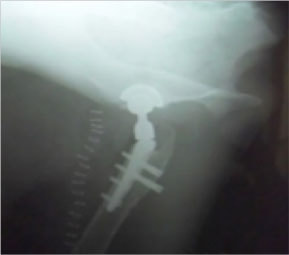

THR法を実施した症例のレントゲン写真

当院では、スクリューを使用し人工関節を固定する Kyon社 Zurich セメントレスTHRシステムが実施可能です。術前に評価した患者の骨格に合わせて、専用のテンプレートで人工関節のサイズを決定します。人工関節として寛骨臼にカップを設置し、大腿骨にステムを挿入し、大腿骨-寛骨臼間の距離に合わせてヘッドを設置します。